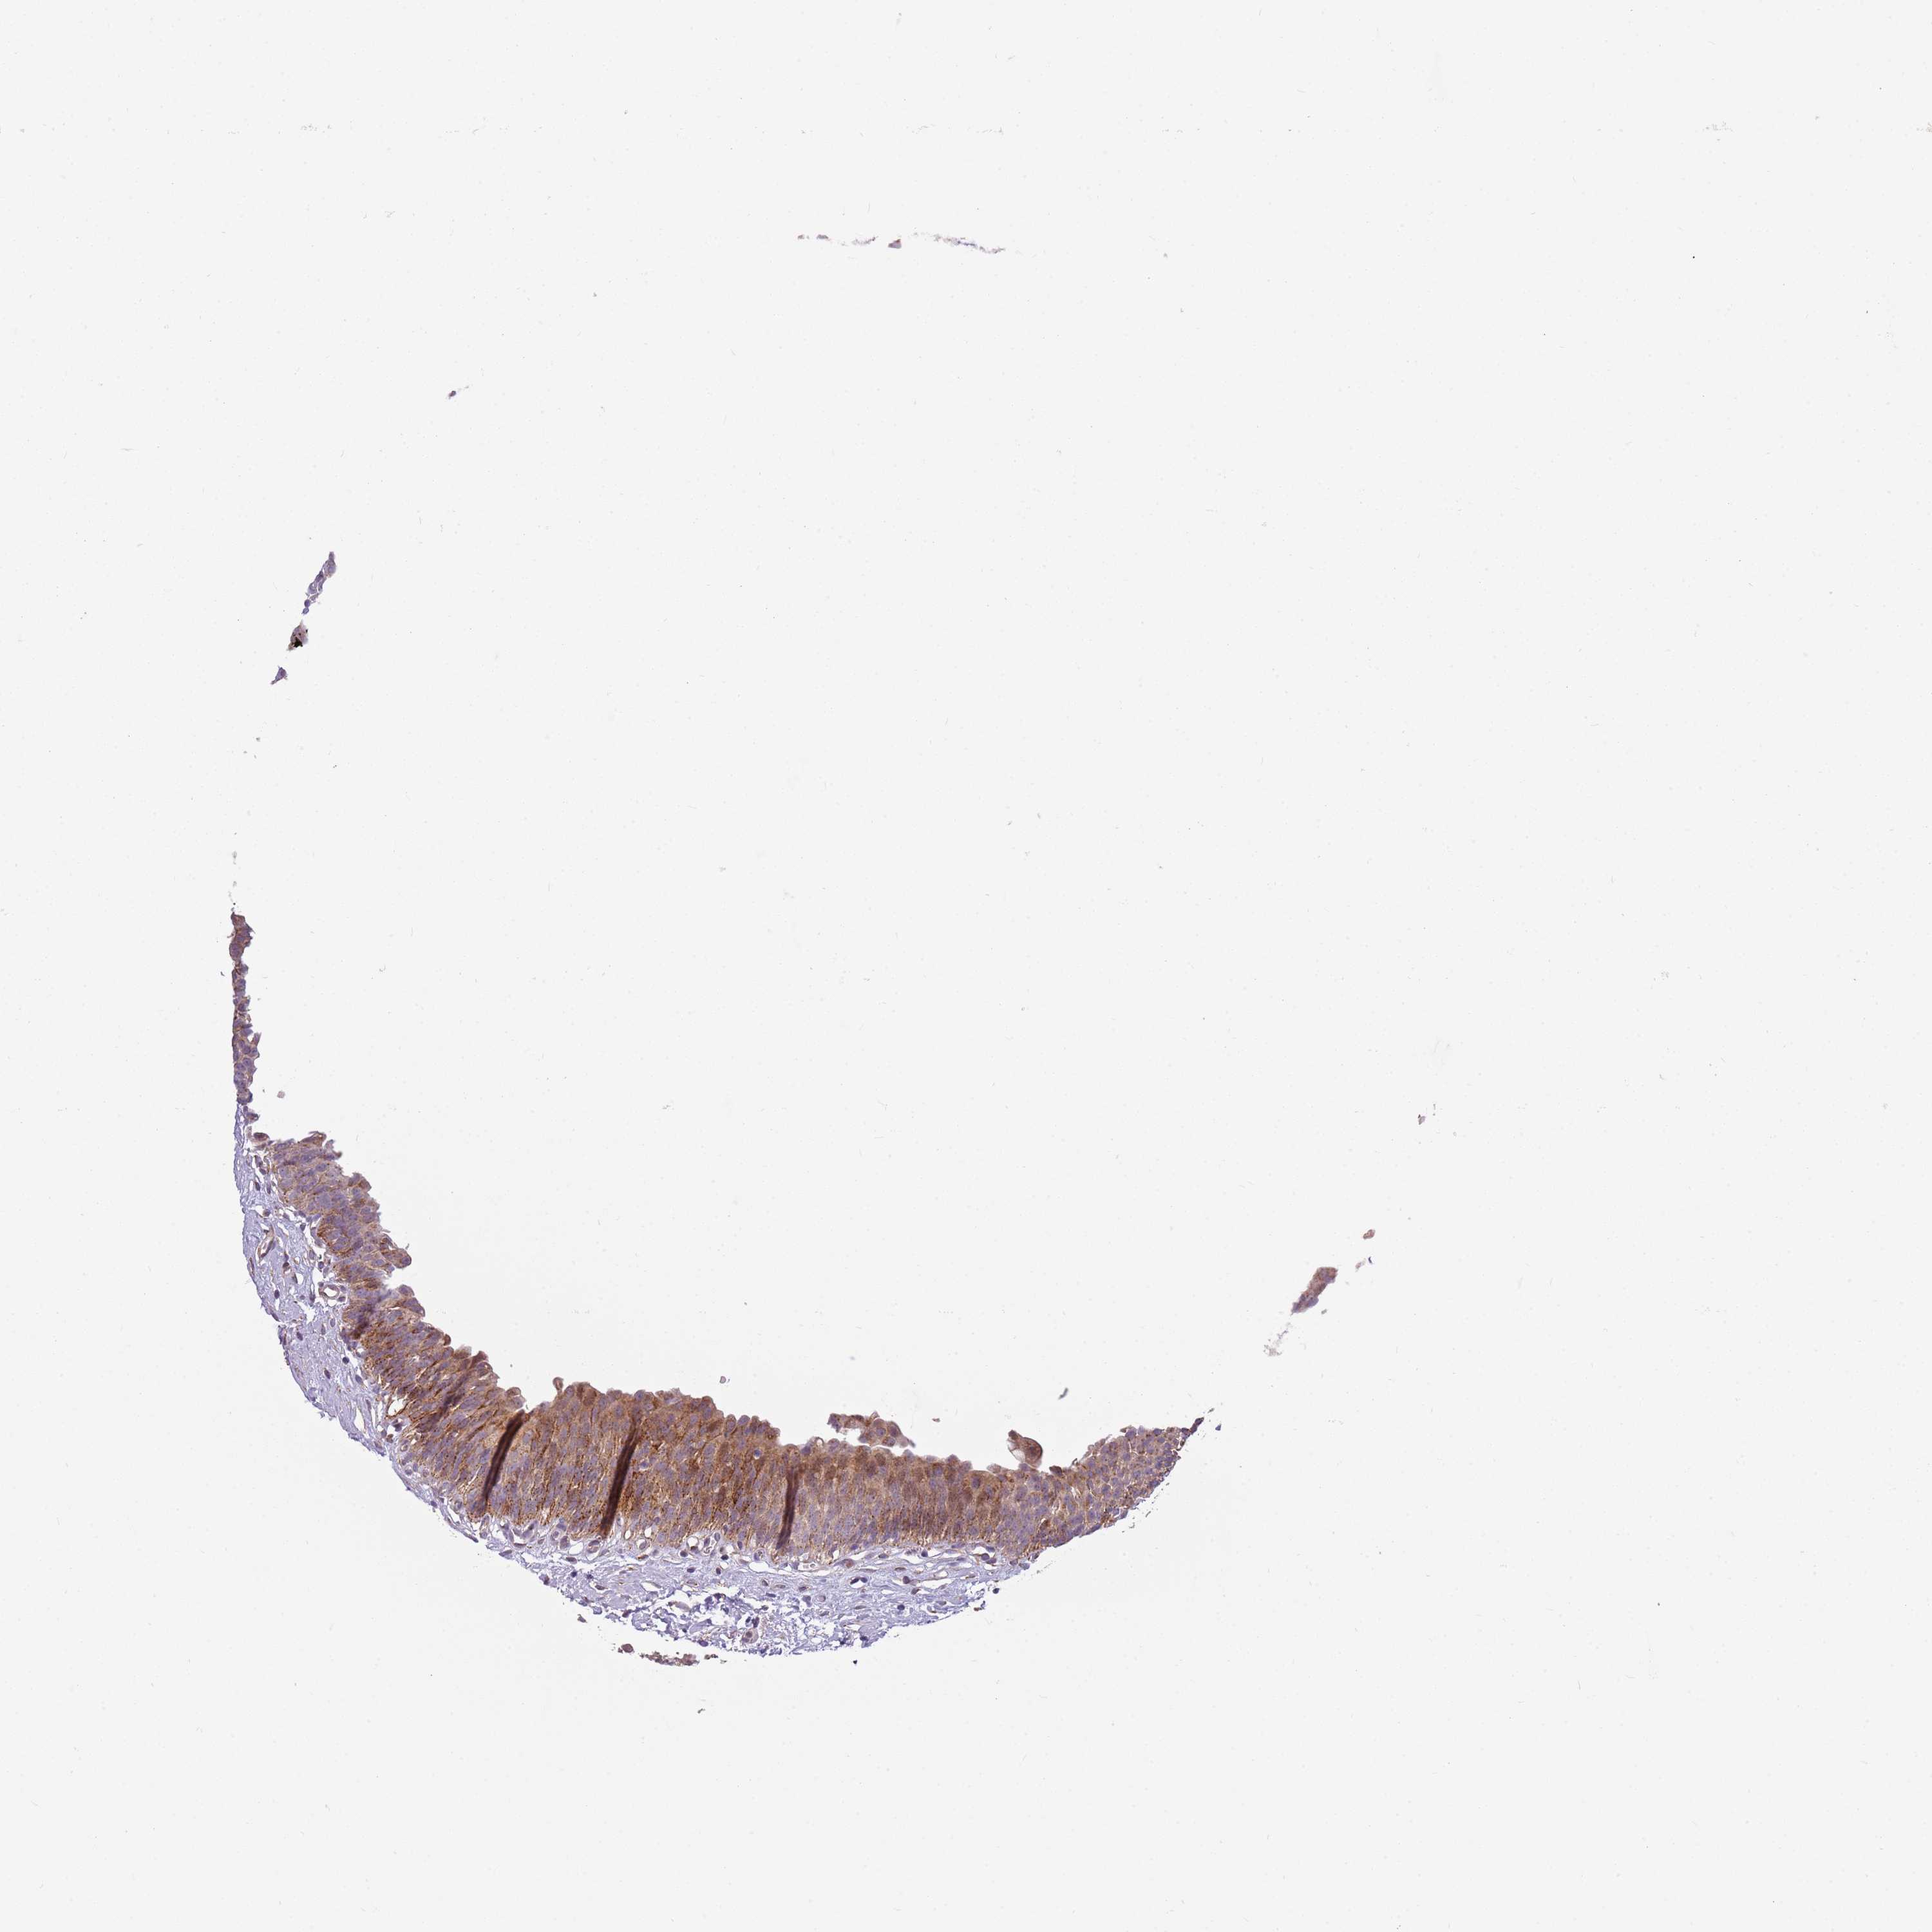

URINARY BLADDER - Antibody stainingi

Antibody staining in the annotated cell types in the current human tissue is reported as not detected, low, medium, or high, based on conventional immunohistochemistry profiling in selected tissues. This score is based on the combination of the staining intensity and fraction of stained cells. Each image is clickable and will lead to virtual microscopy that enables deeper exploration of all samples and also displays staining intensity scores, fraction scores and subcellular localization as well as patient and tissue information for each sample.

Antibody HPA047497

Urothelial cells High